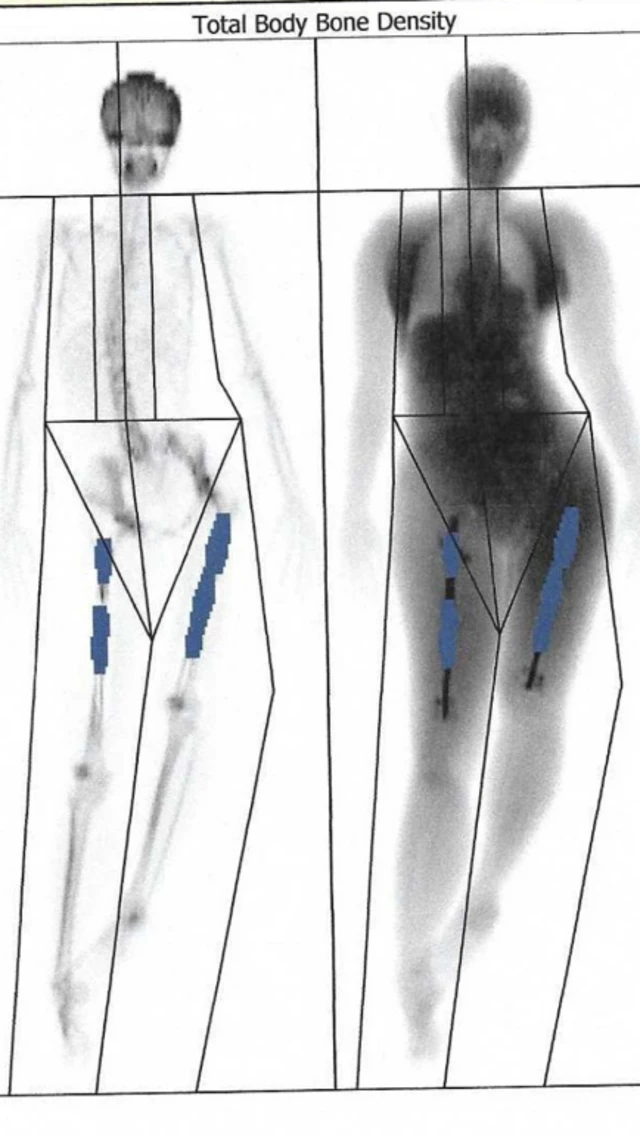

સપ્ટેમ્બર સુધી તેમનો જમણો પગ સાત સેન્ટીમીટર સુધી વધી ગયો હતો. પણ બધું જ સામાન્ય નહોતું ચાલી રહ્યું. એમના બન્ને પગ લાંબા-ટૂંકા થઈ ગયા હતા અને એના લીધે તેમનું કરોડરજ્જુનું હાડકું આડું થઈ ગયું હતું. તેમને સતત દુ:ખાવો થવા લાગ્યો હતો.

છ સપ્તાહ બાદ કરાયેલા સ્કૅનમાં તેમને માલુમ થયું હતું કે એમના જમણા પગનાં હાડકાં વધતાં અટકી ગયાં. આ પગમાં ફીમરના બે ટૂકડા રૉડથી જોડાયેલા હતા.

હાલ ઇલેનની પ્રથમ સર્જરીને આઠ વર્ષ વીતી ગયાં છે. ઇલેન કહે છે કે તેઓ હજુ પણ આ મેડિકલ પ્રક્રિયાથી થયેલી શારીરિક અને માનસિક પીડાથી બહાર નીકળવાનો પ્રયાસ કરી રહ્યાં છે. તેઓ કહે છે કે શારીરિક હિલચાલમાં કેટલીય સમસ્યાઓ છે અને તેઓ પૉસ્ટ ટ્રૉમેટિક સ્ટ્રેસ ડિસઑર્ડર (પીટીએસડી)થી પીડિત છે.